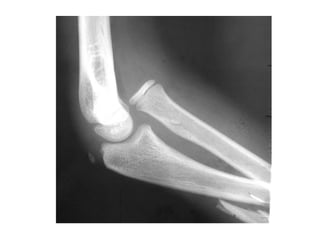

Course of Radial Nerve

• Enters the forearm anterior to lateral epicondyle

– More specifically over articulation between capitulum and

radial head

• ECRB innervated distal to elbow joint either PIN or

superficial branch

• At some point 3cm above or below divides into:

– Superficial radial

– PIN